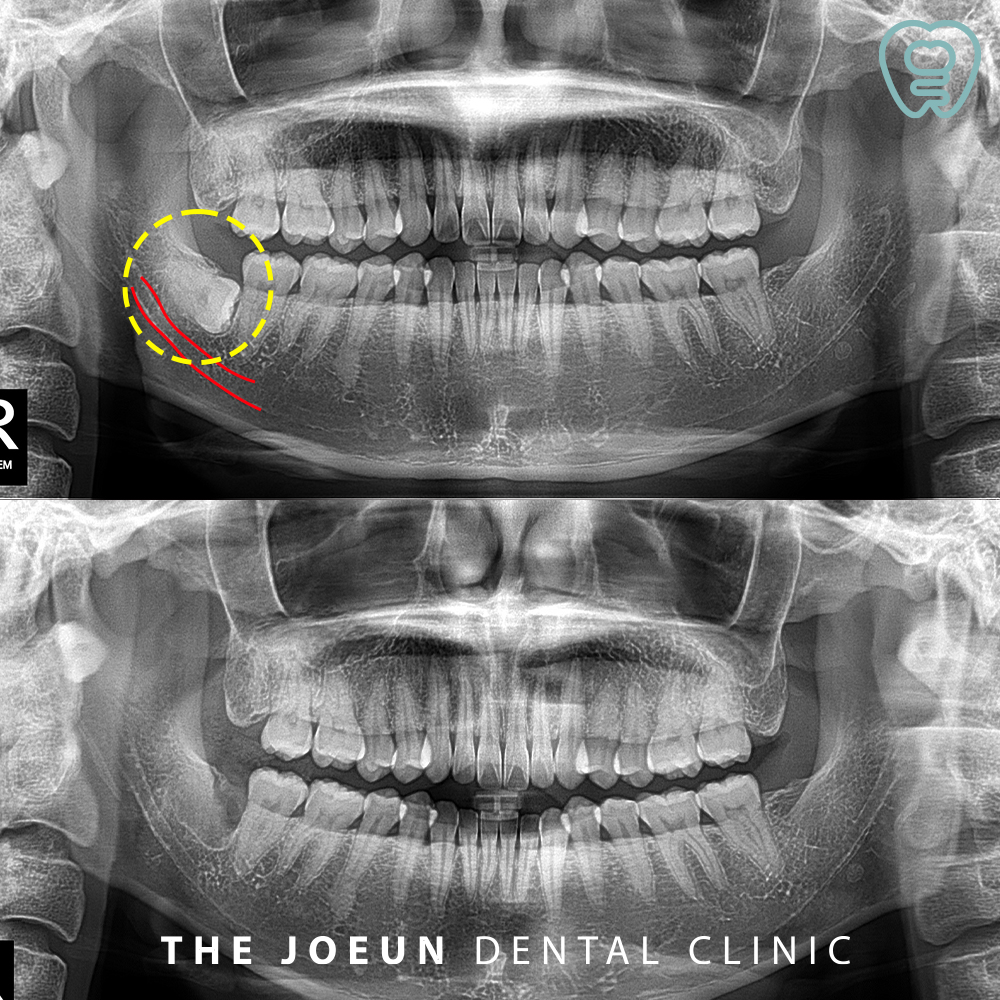

오늘은 오른쪽 아래 잇몸 깊숙이 완전히 매복되어 있는 사랑니를 발치하신 환자분을 소개해 드리려고 합니다.

환자분께서는 전체 검진을 위해 내원해 주셨는데요. 사랑니의 존재를 알고 계셨지만 큰 불편함이 없으셔서 놔두셨다고 합니다. 하지만 파노라마를 촬영해 보니 장기적으로 보았을 때 옆에 붙어 있는 어금니에 좋지 않은 영향을 줄 수 있을 것이라고 판단되어 발치를 권유드려 진행하게 되었는데요.

가장 안쪽에 누워 있는 사랑니이다 보니, 모두 조각을 내어 발치를 진행하였습니다.

주변의 조직과 인접치에 손상없이 말끔하게 발치를 완료하였습니다.